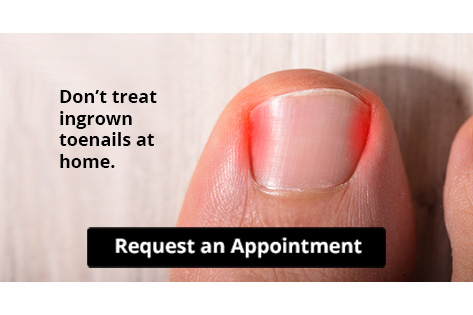

Let the Expert Treat Your Ingrown Toenails